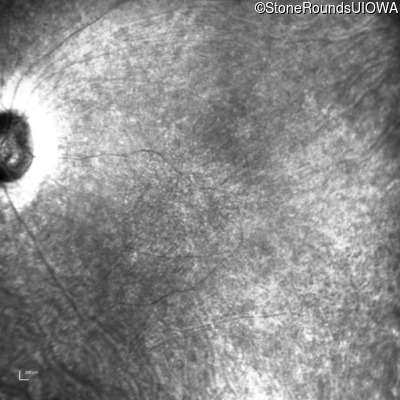

Infrared Fundus Photograph - Left - 20/50

Exemplar